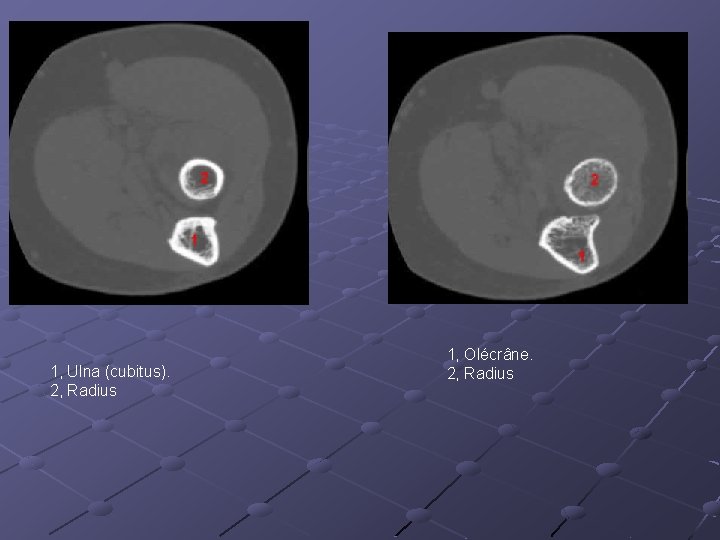

1, Ulna (cubitus). 2, Radius 1, Olécrâne. 2, Radius